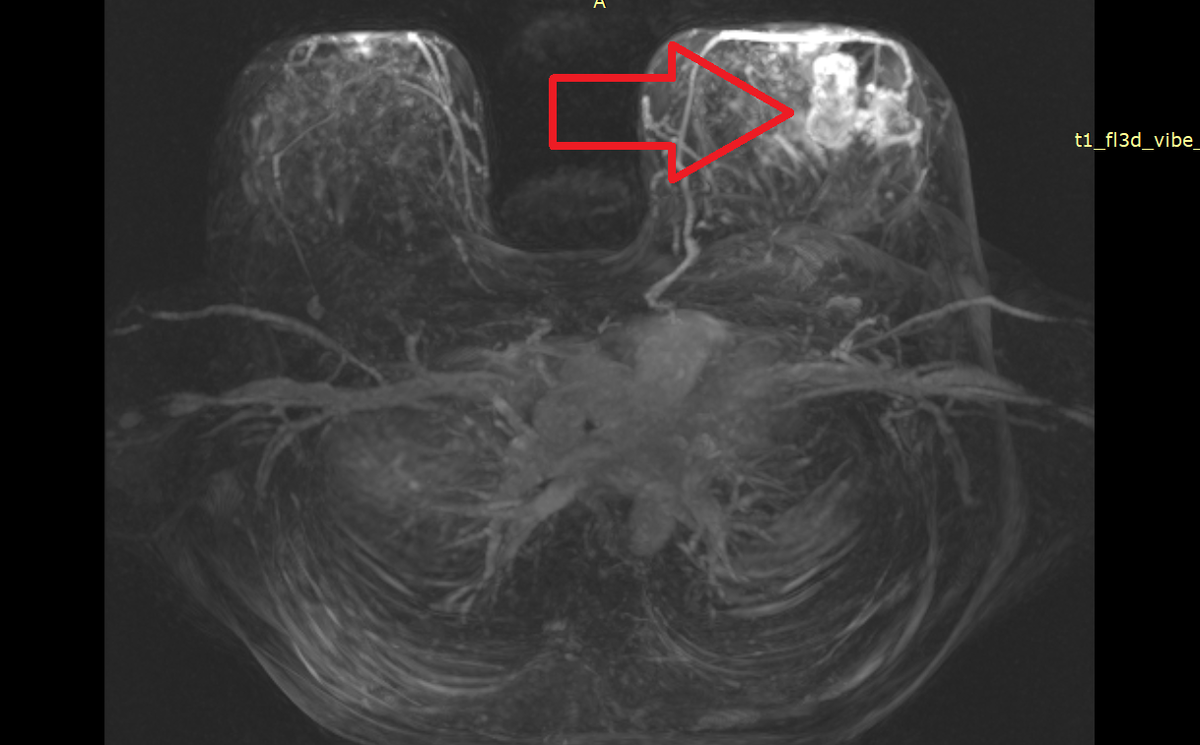

РЕЦИДИВ МАСТИТА СПУСТЯ 10 ЛЕТ ИЛИ ОПУХОЛЬ? СЛУЧАЙ ИЗ ПРАКТИКИ ...